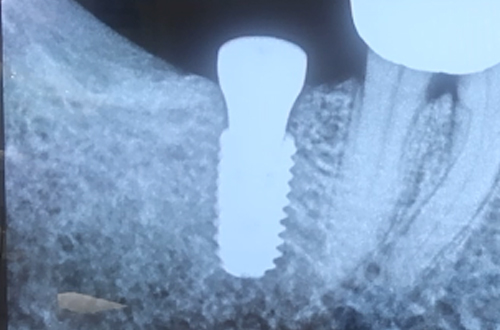

왼쪽 아래 치아를 발치하고 싶어 내원해주셨습니다. 내원 당일 왼쪽 썩은 어금니를 발거하면서 사랑니를 함께 발거 하셨습니다. 이와 동시에 반대쪽 임플란트 식립 상담을 진행하셨는데요. 10년 전 오른쪽 치아를 발거하셨고, 이 빈공간에 임플란트를 식립하기로 계획하였습니다. CT촬영을 판독해본 결과 뼈의 높이와 폭이 충분하다고 판단이 되어 무피판 임플란트 수술을 진행하였습니다. 잇몸의 두께가 충분하여 잇몸 절개 없이 임플란트를 식립해 드렸으며 힐링어버트먼트라고 하는 것을 장착해서 잇몸이 잘 치유가 될 수 있도록 하였습니다. |